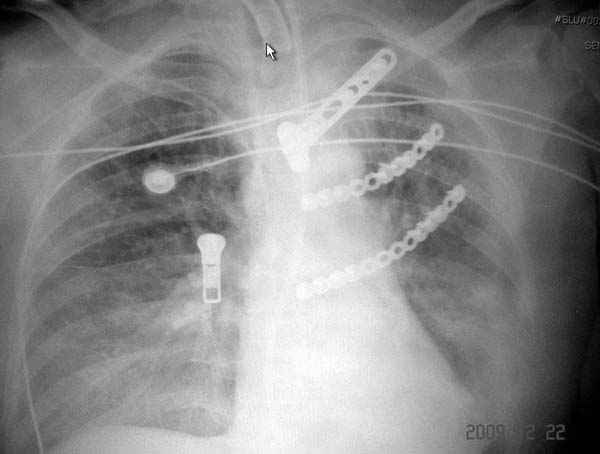

К нам поступила больная 56 лет после автоаварии в бессознательном состоянии, которая срочно заинтубирована в приемном отделении и сделаны необходимые исследования. Данные КТ и рентген показали перелом дистального бедра и Dissociation upper extremity - закрытый отрыв левой верхней конечности на уровне грудинно-ключичного сочленения и множественные переломы ребер.

На поверхности грудной клетки из-за полного разрыва грудной мышцы под кожей заметно биение сердца и след от ремня безопасности. Грудная клетка расширена из-за смещения верхней конечности вверх и латерально. Признаков васкулярного повреждения нет, и из-за отсутствия сознания не смогли определить наличия повреждения нервов.

Срочно в операционной наложен наружный фиксатор и травма хирургом поставлены трубки в плевральную полость.

На седьмые сутки нами совместно с торакальным хирургом сделана операция по фиксации грудинно-ключичного сочленения и переломов ребер.

После кожного разреза обнаружили полный разрыв грудной мышцы и повреждение перикард от уровня второго до восьмого ребер. Хирург находился с нами и после нашей работы зафиксировал повреждение перикарда и разрыв грудной мышцы.

Не все переломы ребра фиксированы, и поэтому хотели услышать комментарии тех, у кого имеется опыт.

Больная в данный момент с трахеостомой, стабильная, пришла в сознание. На сегодняшнем осмотре больная шевелит пальцами, что говорит об отсутствии повреждений нервов.

Пластина из Synthes http://int.synthesmatrixrib.com/html/Overview.5.0.html